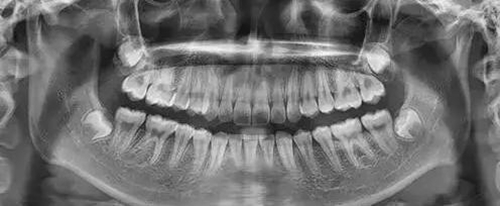

為了幫助矯正醫(yī)生準(zhǔn)確的分析患者的具體情況,醫(yī)生需要幫準(zhǔn)備矯正的患者拍攝全景牙片以及頭顱側(cè)位片。

作用:通過全景片我們可以看到牙齒的數(shù)目是否有異常情況(例如:主要是頜骨內(nèi)有無多生牙,埋伏牙等),牙根的情況(如:包括形態(tài),位置,牙根有無吸收等),牙槽骨的情況,牙周組織的健康狀況,髁狀突的狀態(tài)等。

頭顱側(cè)位片的參考價(jià)值與全景片一樣重要,在頭顱側(cè)位片上我們可以直接測(cè)量上下頜骨畸形的程度,分析引起錯(cuò)合畸形的原因是頜骨的問題還是單純的牙齒問題,測(cè)量?jī)?nèi)容包括硬組織和軟組織的測(cè)量,這些數(shù)據(jù)是擬定治療計(jì)劃的重要信息,在治療計(jì)劃的確定上起到了舉足輕重的作用。